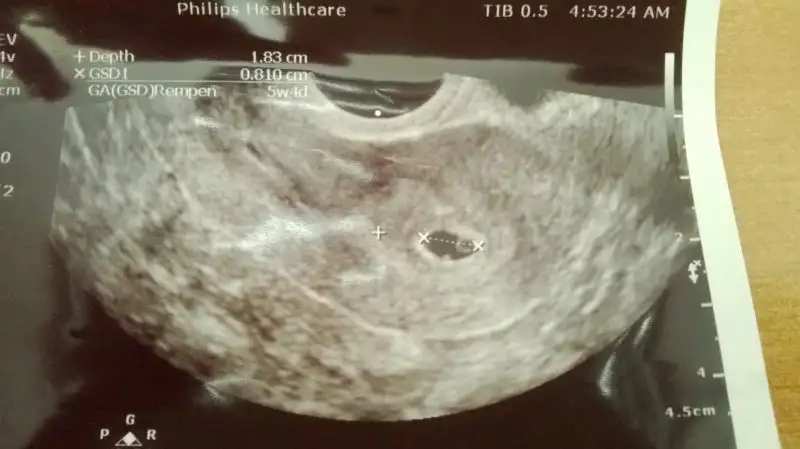

Erkek canımbu durumda benmki ne oluyor vajinal ultrasonla bakıldı

Hafi hayırlı olsun..Ramzi teorisine göre ( bilimsel bir araştırma sonucuymuş ve %85 doğruluğu varmış). İlk 6-8 haftalık ultrason görüntüsüne göre bebeğin kesenin içersinde soldan ya da sağdan girişine göre cinsiyet tahmini yapılıyor. Bilimsel olunca tecrübeli annelerimiz yada anne adaylarımızdan yardım istiyoruz. Doğruluğu var mı öğrenmek adına :) Bizleri aydınlatırsanız çok seviniriz. bu teorieye göre;

Vajinal muayeneyle bakıldıysa eğer;

Sağdan girmiş gözüküyosa aslında solmuş ve ERKEK,

Soldan girmiş gözüküyosa aslında sağmış ve KIZ ,

bu durumda benmki ne oluyor vajinal ultrasonla bakıldı

YANLIZ BEBEK küçün nokta şeklinde olan diğer halka gibi olan yolk kesesiErkek canım